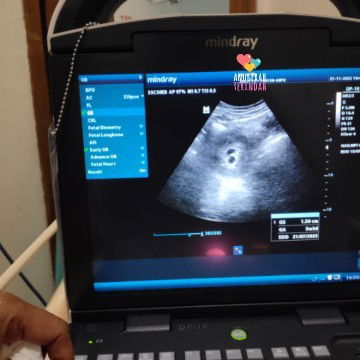

Ini ada 2 kantung janin apa satu tapi terhalang jadi seperti 2 kantung.

2 kantung janin apa satu ya Bun? Kalo 2 kenapa ya? Ini usia 5 week lebih #seriusnanya #bantusharing

mungkin kembar bun. krn 2 kantung